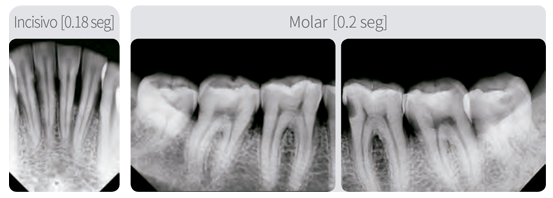

El EzRay Air C (de sillon) es un dispositivo ligero de rayos X, diseñado para un fácil manejo y un posicionamiento estable, brindando una calidad óptima de imagen de rayos X intraoral. El cabezal de tubo ligero del EzRay Air C proporciona a los usuarios un sistema estable para un uso seguro y fácil de la fuente de rayos X maximizando la claridad de la imagen y optimizando el flujo de trabajo.